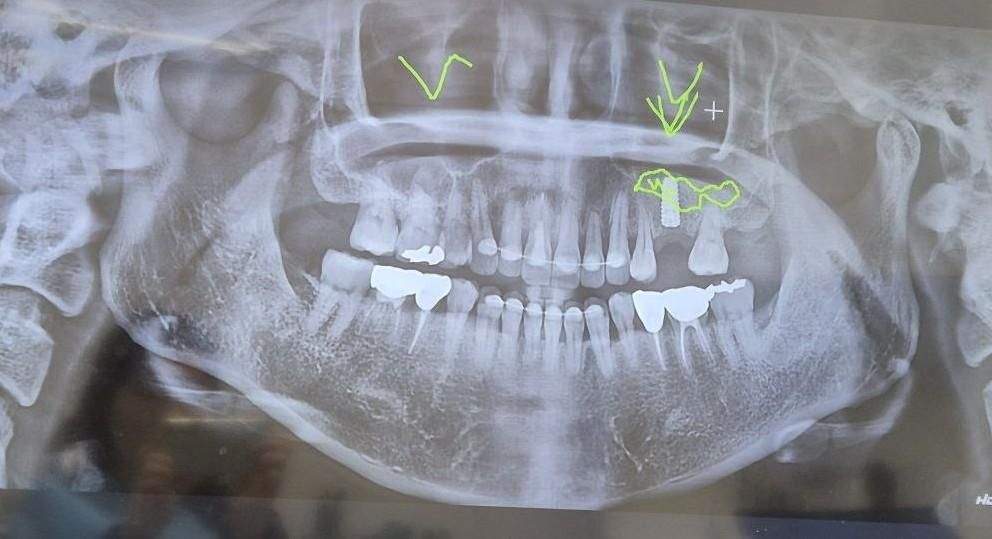

#26번 치아 2달 전 상악동거상술 + 임플란트 식립하였습니다.

기존 뼈 3~4mm 수직거상술로 10mm짜리 식립한 것으로 알고 있습니다.

수술 전 ct에서는 상악동이 깨끗하다고 하셨고 축농증 증상은 없었습니다.

수술한 치과에서 엑스레이, ct촬영하였는데 선생님은 뼈이식한 것은 문제가 없고 가벼운 상악동염 증상같다고 빨리

낫고 싶으면 이비인후과를 가서 약을 타먹어보라고 하셨습니다.

이비인후과 의원에 가니 이비인후과 ct가 더 정확하다고 해서 다시 촬영하였는데 상악동 염증이 없기 때문에

약을 줄수 없다고하십니다. 치아뿌리 쪽 점막 부은 것은 문제가 안되고 코이물감과는 상관이 없다고 해서 그냥 나왔습니다.

치과에서는 이정도 붓기? 염증은 코감기만 걸려도 보이는 증상이라고 하시고 보철 올리는 것과 상관이 없다고 하시는데 수술하고 두 달째 불편한 느낌이 안 없어져서 답답합니다. (1달 뒤 2차수술 예정)

• 1번 째 사진

1. ct상으론 거상, 뼈이식, 식립 모두 양호하게 잘 된것 같습니다 술후 부종이 두달 가는건 흔치 않은데 감염 가능성도 고려해봐야 할 것 같습니다